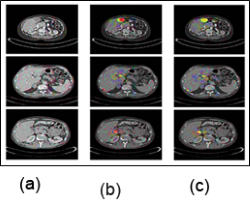

Figure 7: a) Test picture (b) Segmentation output using the suggested HFCNN (c) Malignancy diagnosis on a hepatic image.[1]

The weights of the probability uniformly, and fresh images are resampled using the nearest neighbor approach. Figure 7(b) Depicts the segmentation results using the HFCNN approach[1]. For each image in our collection, four measurements were created on a different scale. Figure 7(a) Depicts the segmentation of a liver tumor. Figure 7(c) Depicts malignancy identification using stones.